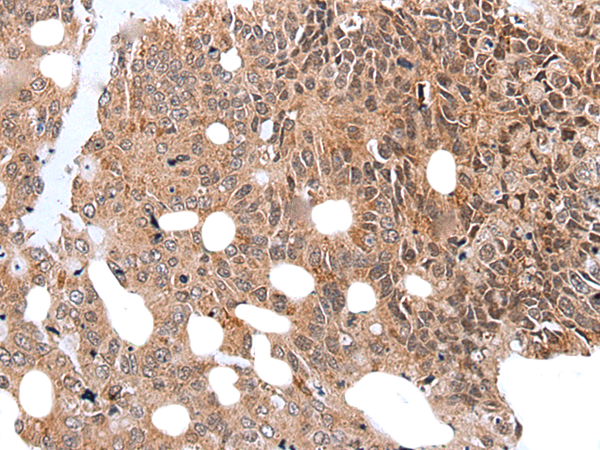

分类: 科研抗体货号: P12855别名: LRPDIT; LRP-DIT应用: IHC反应种属: Human, Mouse